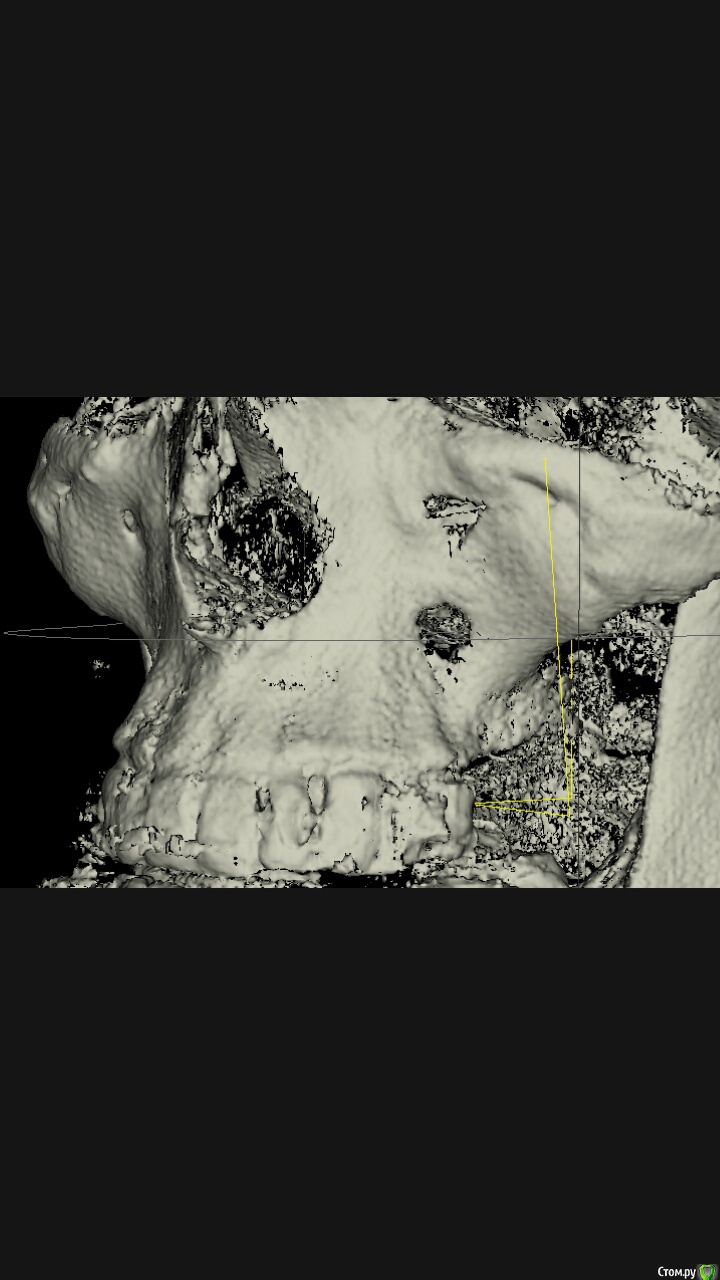

Jurai Опубликовано 18 сентября, 2015 Поделиться Опубликовано 18 сентября, 2015 Ещё и как делают. Я теперь любуюсь на томограмму, где через полгода после операции окно доступа во всю переднюю стенку, и не представляю что дальше мне с этим пациентом делать. За полгода никакой регенерации не получили, не думаю, что что-то изменится сильно в лучшую сторону. Ссылка на комментарий